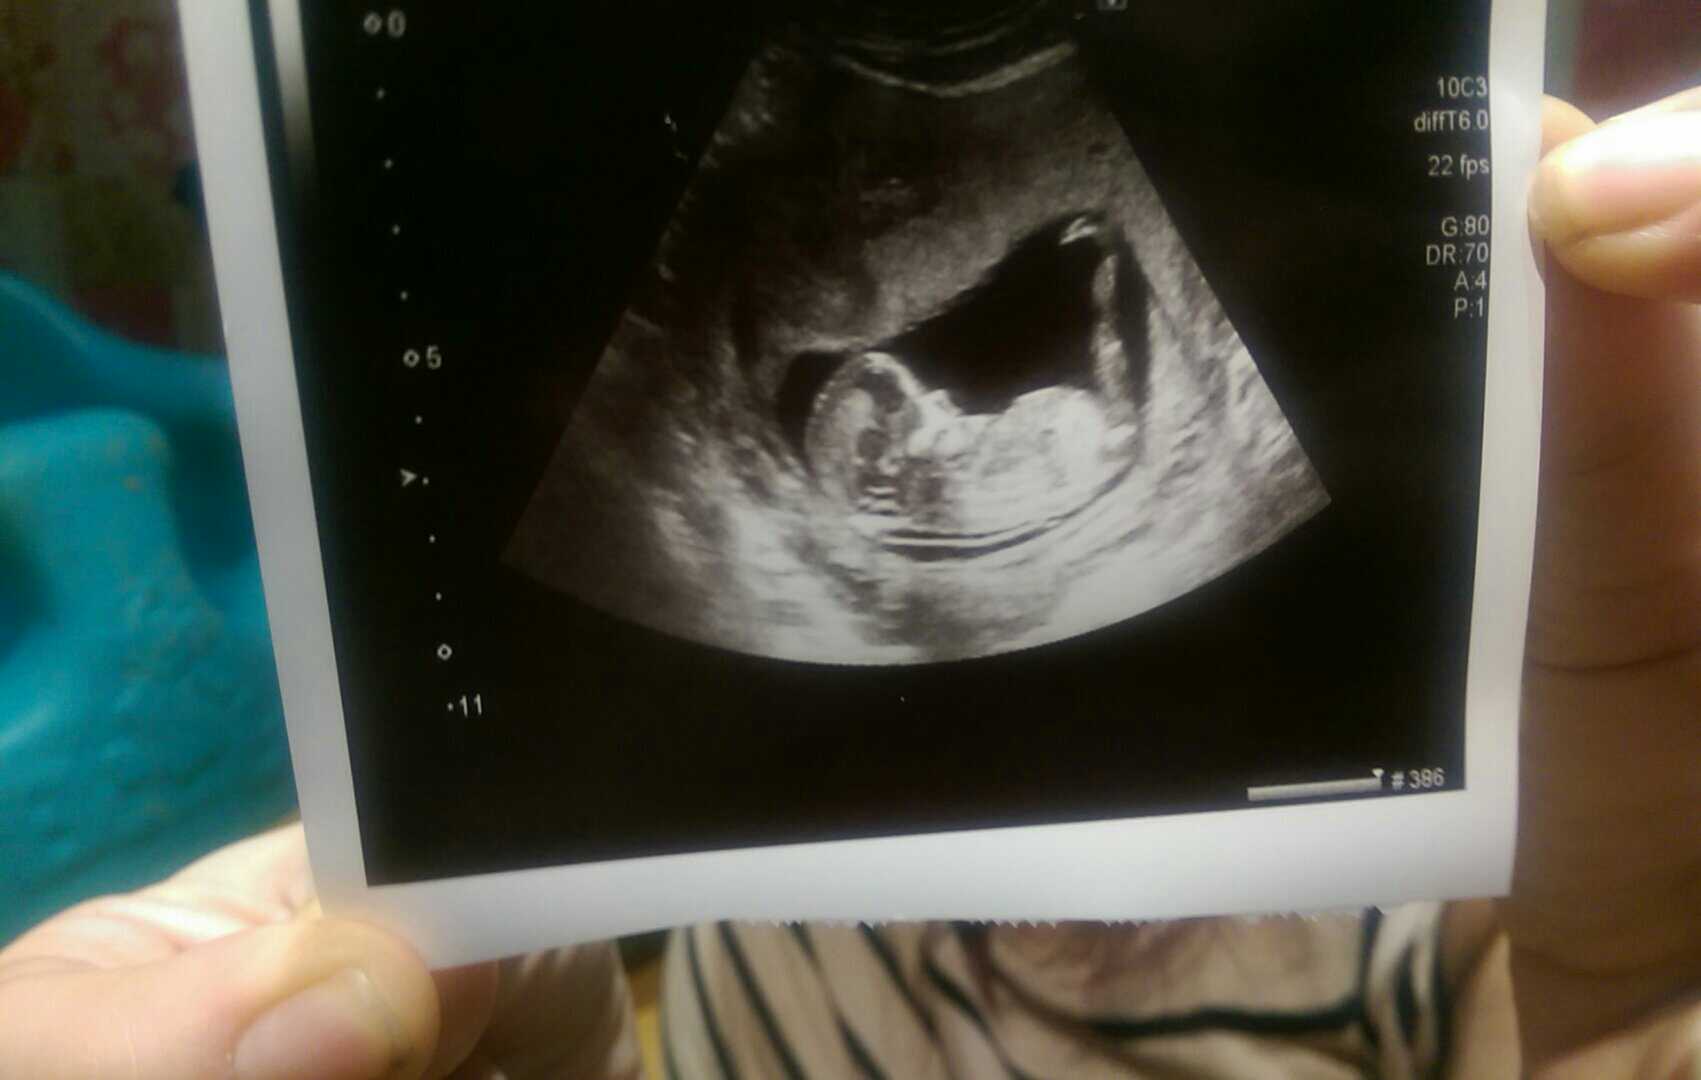

Any guesses for my 13 week nub shot please :)

Attachment 29303

It's a Girl xx